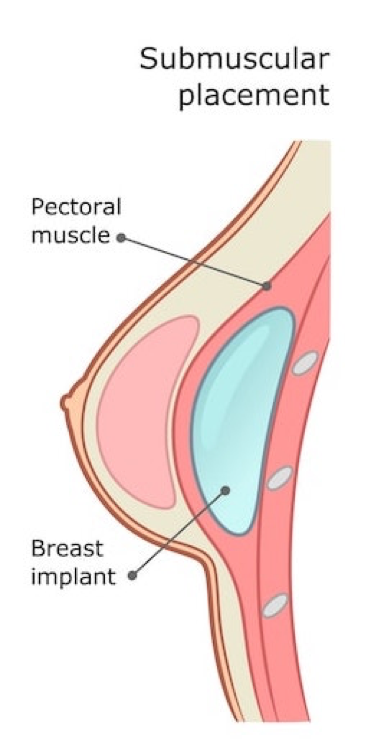

Submuscular

Submuscular implants are implants that placed under the pectoral muscle and the breast tissue. The main rationale behind sub muscular placement is to provide greater coverage of the implant and to create a more natural “takeoff” that blends with the natural breast tissue. There are a number of pros and cons of under the muscle implant placement:

- When smooth implants are used—which is all the time for Dr. Richardson—the capsular contracture rate for under the muscle placement has been found to be lower than other implant placements.

- Mammograms with under the muscle implants are more accurate according to anecdotal evidence from technicians and patients.

- There is a lower risk of implant visibility with a submuscular placement due to the additional coverage provided by the muscle.

- Under the muscle implants can provide a more teardrop look due to the compression of the upper-pole creating a more gradual, sloping “take-off” of the implant.

- Under the muscle implant placement has a slightly longer breast augmentation mammoplasty recovery, and slightly greater discomfort following surgery due to the muscle interference.

- There is visible animation when patients are doing physical activity or using the pec muscles with a submuscular placement.

Submuscular placement is often suitable for patients with little-to-no breast tissue, as implant visibility is more of a concern for these patients. Submuscular placement is also appropriate for patients having a breast lift mastopexy, as this approach optimises blood supply.